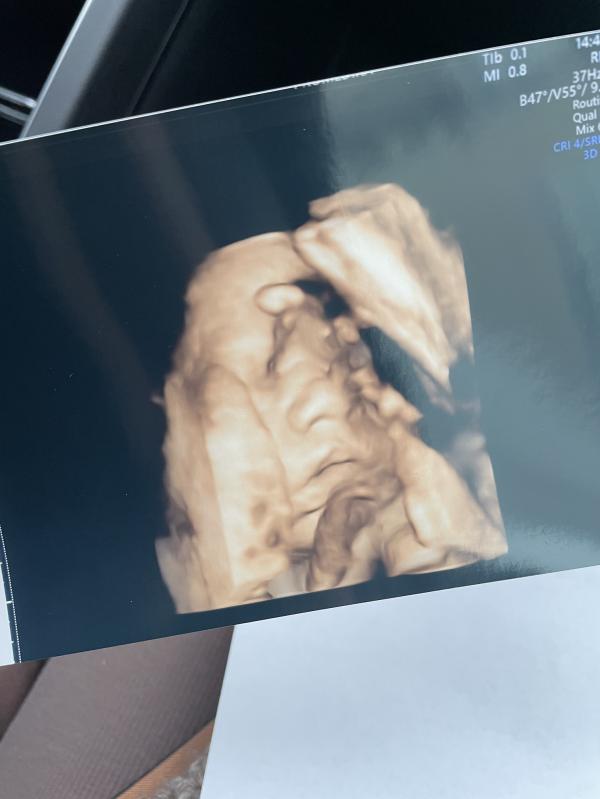

Была сегодня на 3 скрининге 😻❤️

По месячным Срок 29 и 6 дней

По узи срок 31 и 2 дня

Вес 1750 кг

Пдр 04.04.2022

Все в норме ❤️

Прятал личико, закрывал руками постоянно, сделали только такую фотографию , минут 15 не получалось никак 😀 спросила на счёт контракта , так как была у Беляевой, она раньше принимала роды, сейчас увы уже не принимает роды , сказала, что это не к чему, партнёрские роды сейчас не разрешают , на счёт палаты , сказала можно со схватками приехать и уже договориться , вообщем ду...